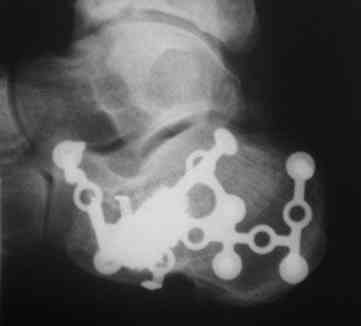

Разница между информацией полученной Р-графески и КТ - огромная.

Пример.

PDF, 134 Kb

Б-ной прооперирован по АО, применялась аутопластика из крыла подвздошной кости. На фото больной через 1 мес. Через 4 мес. - физический труд, осмотр через год - жалоб и претензий нет. До нас обращался в два лечебных учреждения, перелом не диагностирован. Был суд. Пациент процесс выиграл.

Больной гражданин РФ. Травма в Казахстане, здесь же и оперирован.

Виктор.